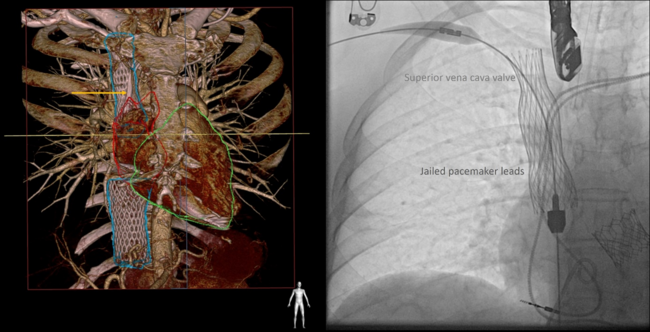

A transcatheter CAVI was performed. A 60-mm superior vena cava prosthesis encased the pacemaker leads upon their emergence from the left subclavian vein. Fluoroscopic imaging confirmed the entrapment of both pacemaker leads within the stent structure, a phenomenon known as "jailing" (Figure, Video). The initial post-deployment assessment showed normal lead function without dislodgment or significant impedance changes. The potential risks associated with lead jailing include lead fracture, insulation breach, and compromised sensing or pacing capabilities over time. At the 1-year follow-up, there was no variation in the lead impedance measurements.